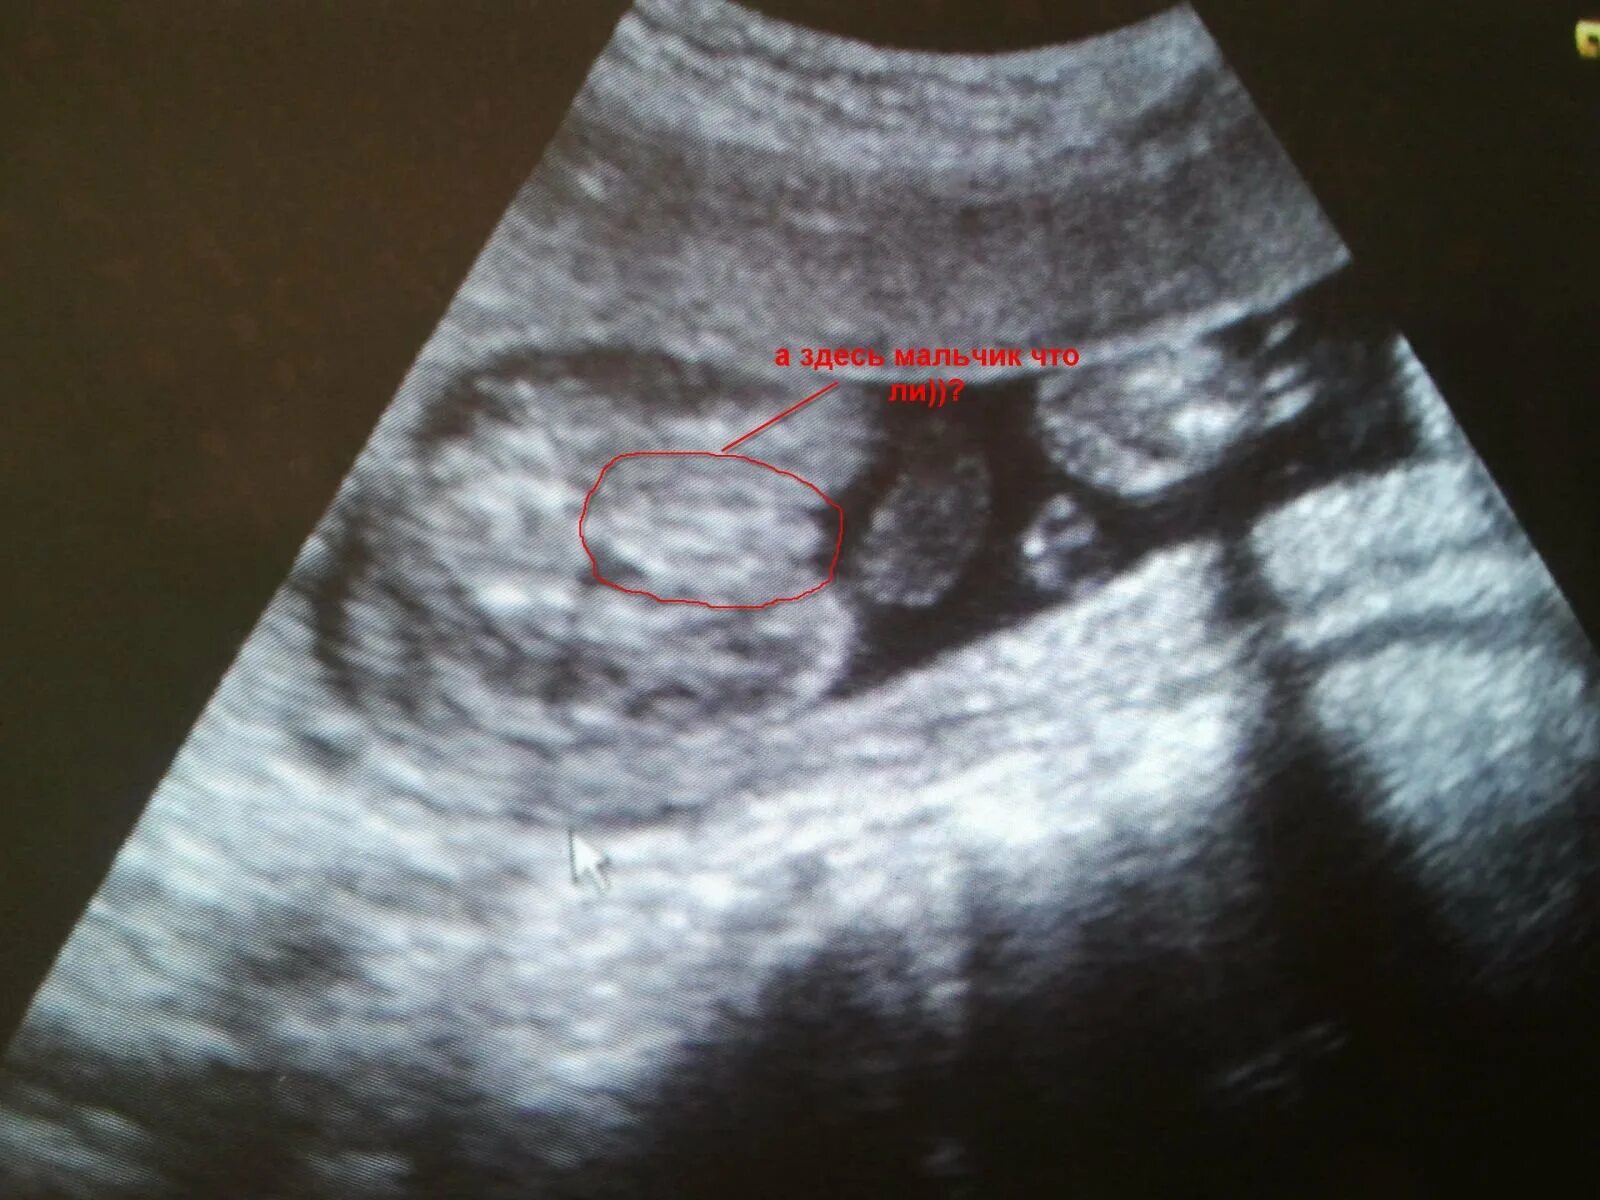

20 недель ошибка пола